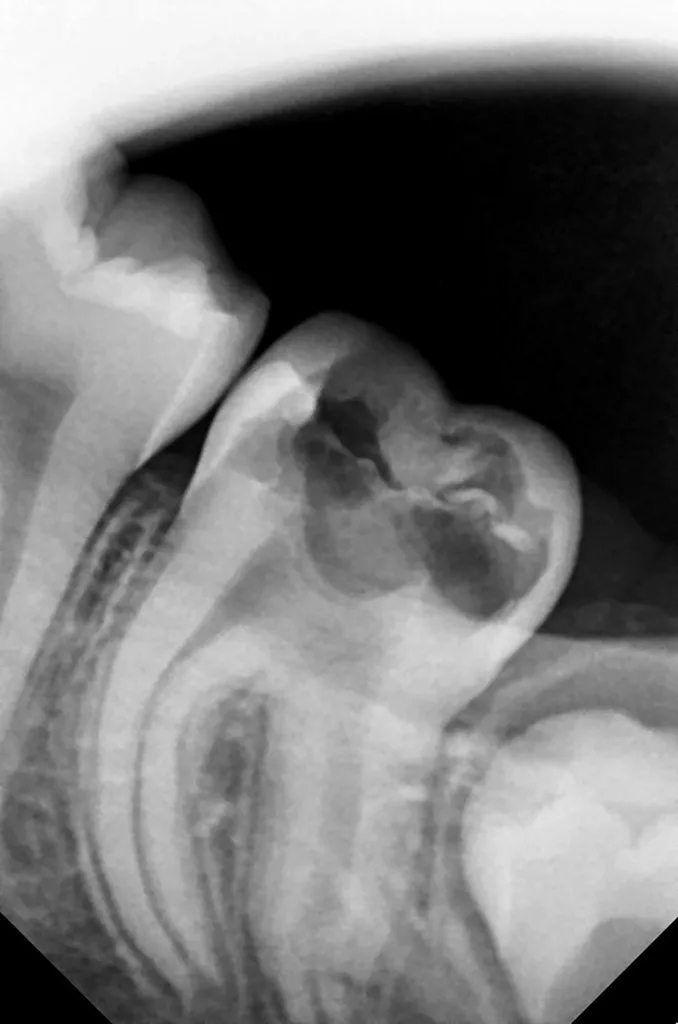

Bei routinemäßigen Röntgenkontrollen ergeben sich manchmal Zufallsbefunde unklarer Genese. So stellt sich beispielsweise bei der Betrachtung der Abbildung 1 die Frage, wie sich ein Zahnhartsubstanzdefekt so schnell entwickeln konnte. Ein weiteres Röntgenbild (Abb. 2), das vor dem Zahndurchbruch aufgenommen wurde, zeigt jedoch, dass es sich in diesem Fall nicht um Karies, sondern um die sogenannte präeruptive intrakoronale Resorption (PEIR) handelt. Für diesen Befund finden sich in der Fachliteratur auch noch andere Bezeichnungen wie „idiopathic external resorption of unerupted permanent teeth“ [1], „intra-follicular caries“ [2], „radiolucent lesions resembling caries“ [3], „occult caries“ [ 4] oder „pre-eruptive caries“ [5].

V. Slabkovskyi, O. LiutikovJahr vor dem Durchbruch des Zahnes 36.

Das fünfjährige Mädchen stellte sich 2017 zur jährlichen Routinekontrolle vor. Im Rahmen der Untersuchung wurden Röntgenaufnahmen der Milchmolaren gemacht (Abb. 2). Der klinische und radiologische Befund der vor uns früher gelegten Kompositfüllungen war gut, es wurde allerdings eine PEIR an den noch nicht durchgebrochenen ersten bleibenden Molaren festgestellt (Abb. 2). Den Eltern wurde empfohlen, sich unverzüglich bei Beginn des Durchbruchs der ersten Molaren erneut zur Behandlung vorzustellen. Ein Jahr später erschien die junge Patientin schmerzfrei zur Kontrolle. Der Zahn 36 war noch teilweise mit Gingiva bedeckt. Auf einer neuen Röntgenaufnahme (Abb. 1) wurde die PEIR-Läsion mit unveränderter Größe in pulpanahen Bereichen bestätigt (Grad 3 der Läsion nach Seow). Der Zahnschmelz sah intakt aus, es konnte kein pathologischer periapikaler Befund bei den noch nicht ausgewachsenen Zahnwurzeln festgestellt werden. Daraufhin wurden die verschiedenen Behandlungsmöglichkeiten von Fissurenversiegelung bis Vitalerhaltung der Zahnpulpa mit den Eltern des Kindes besprochen.